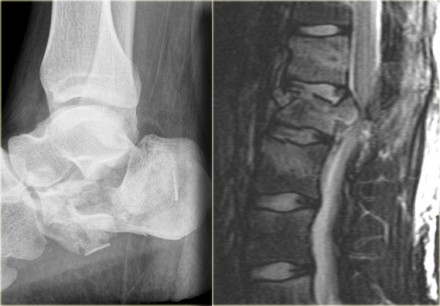

On the left a fracture of the calcaneus and a lumbar spine fracture.

In this case it is clear that we are looking at an unstable fracture, because this is a burst fracture.

Both the anterior and the middle column are disrupted.

In addition there is edema in the posterior soft tissues indicating that there is also involvement of the posterior column.

Notice also the marrow edema in the adjacent bodies due to the severe axial loading.

On the left another example of a Chance fracture.

Chance fracture (3)

On the left a Chance variant.

This is a pure ligamentous injury, which is analogous to bilateral

interfacet dislocation, which is also a pure ligamentous injury.

There is rupture of the interspinous ligament, dislocation of the facet joints and a horizontal rupture of the disc.

Pure ligamentous and combined osseous / ligamentous variants have an increased risk of instability compared to the osseus type.

Always look for a split of the posterior elements, disc widening or widening of the spinous processes and facets.